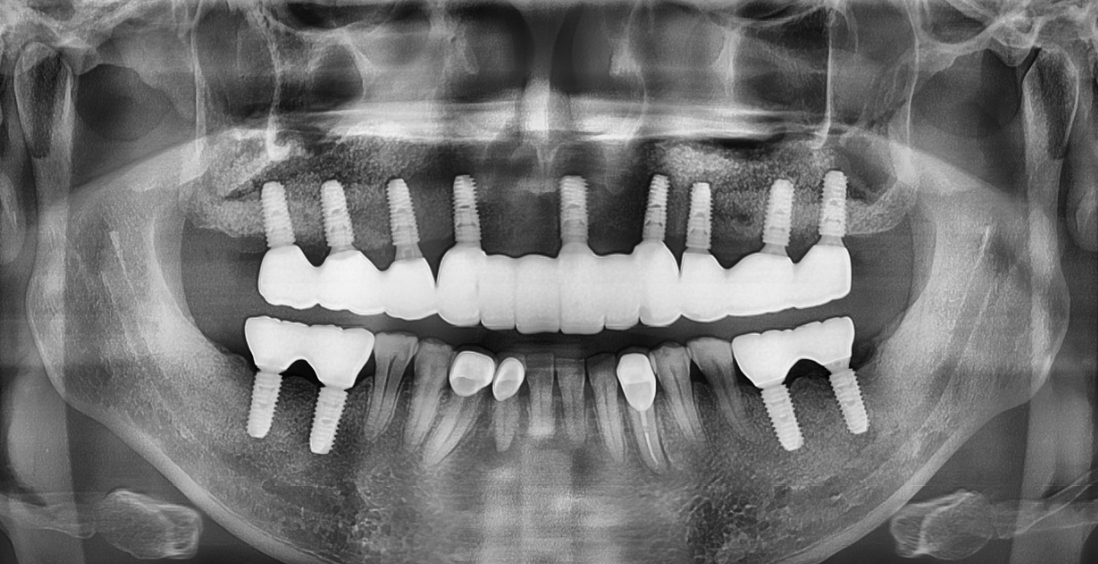

CASE 1 : 전체 임플란트 (치료기간 : 9개월)

*치료과정에서 부작용이 발생할 수 있으므로

정확한 진단과 수술이 요구됩니다.